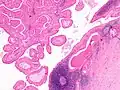

The appearance of this tumor under the microscope is unique. There are cystic spaces surrounded by two uniform rows of oncocytes, which are epithelial cells with abundant, granular, eosinophilic cytoplasm.[7] The cystic spaces have epithelium referred to as papillary infoldings that protrude into them. Additionally, the epithelium has lymphoid stroma with germinal center formation.

This Warthin's tumor presented as a parotid mass in a middle-aged male, who underwent superficial parotidectomy. The tumor, at the right of the image, is well-demarcated from the adjacent parotid tissue and tends to shell out from it.

Histopathology of Warthin tumor in the parotid gland. H&E stain.

Histopathology of Warthin tumor in the parotid gland. Another view of a file "Warthin tumor (1).jpg". H&E stain.